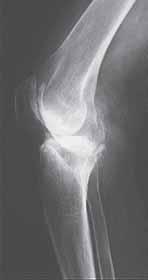

Rycina 14.2. Osteokondukcyjne pobudzenie zrostu kostnego belką i przeszczepami kości allogenicznej złamania okołoprotezowego kości udowej lewej po realoplastyce rewizyjnej stawu kolanowego; a) rentgenogram w projekcji przednio-tylnej (a-p), b) rentgenogram w projekcji bocznej (l).